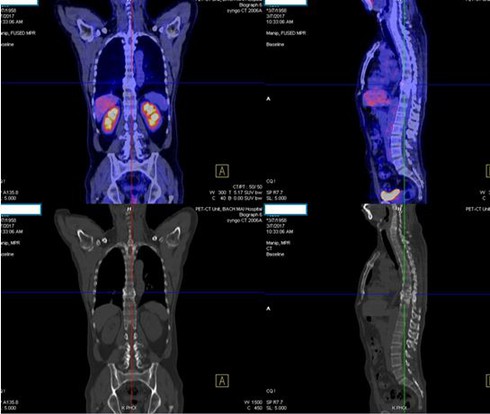

Hình ảnh chụp CT của bệnh nhân H. |

Ông Nguyễn Văn H. 76 tuổi, trú tại Đống Đa, Hà Nội tâm sự ông mới bị ung thư phổi. Bác sĩ chẩn đoán ung thư phổi giai đoạn IV, di căn xương, hạch thượng đòn…

Ông H. cho biết hơn 1 tháng nay, có biểu hiện: Ho khan liên tục nhiều ngày kèm theo tức ngực, khó thở nhẹ, không sốt, đau xương nhiều vị trí ( cột sống, bả vai…). Ăn kém, gày sút cân (4 kg/ 1 tháng).

Khi đến khám tại Bệnh viện Bạch Mai, bác sĩ ghin nhận bệnh án thể trạng gày, da niêm mạc bình thường. Có hạch thượng đòn phải, kích thước 1,5 cm chắc. Phổi thông khí tôt, khó thở nhẹ , nhịp tim đều.

Các xét nghiệm sinh thiết hạch bác sĩ chẩn đoán ung thư biểu mô tuyến của phổi là dạng ung thư phổi không tế bào nhỏ. Xét nghiệm đột biến gen (EGFR): Đột biến tại exon 21 và 19.